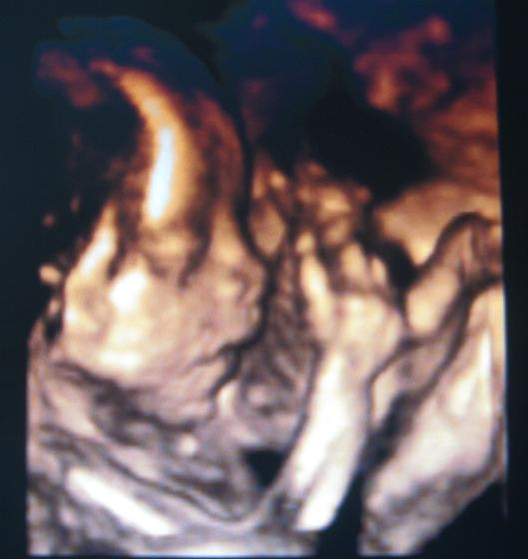

Pola juz po usg połowkowym. Jest zdrowiutka ma już 25 cm razem z nożkami i waży koło 350g. I jets strasznym wiertkiem. Załączam zdjątka

1. stopki